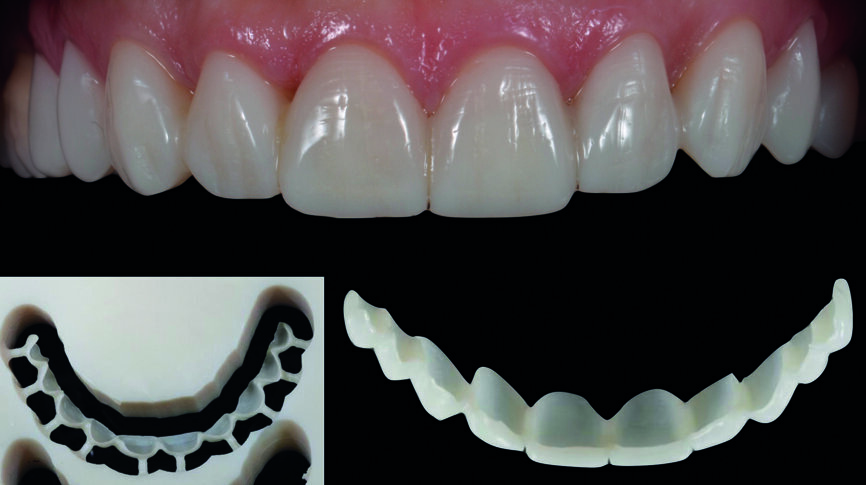

Fig. 14 : Flux de travail numérique (modèle imprimé en 3D, facettes réalisées en technique CFAO, ajustements, coloration/glaçage).

| Fig. 15a : Facettes en céramique feldspathique avec pâte d‘essai

Fig. 15b : Facettes réalisées en technique CFAO avec pâte d‘essai.

| Fig. 15c : Facettes en céramique feldspathique du premier quadrant et simultanément, facettes réalisées en technique CFAO du second quadrant avec pâte d‘essai.

Le jeu de facettes en céramique feldspathique a été fabriqué en IPS Style (Ivoclar Vivadent) sur un modèle en plâtre-pierre, tandis qu‘un bloc IPS Empress CAD Multi (Ivoclar Vivadent) a été utilisé pour le jeu numérique (Figs. 13 et 14). Les deux jeux ont été évalués en bouche avec une pâte d‘essai afin de comparer les propriétés optiques des facettes feldspathiques et des facettes réalisées en technique CFAO (Figs. 15a–c).